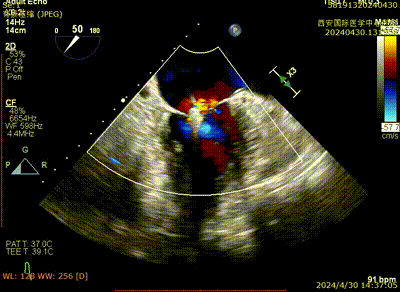

术后二尖瓣反流评估

术后结果